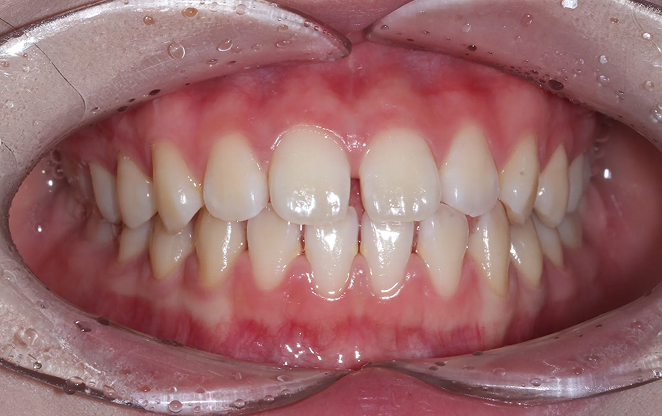

Before

After

어려운 결정을 내리지 않고도 아름다운 미소를

찾아갈 수 있는 길이 있습니다. 비발치 교정은 발치를 하지 않고

치아를 이동시켜 공간을 확보하는 방법입니다.

치아의 배열을 세심하게 조정해 공간을 확보하고,

치아가 자연스럽게 자리할 수 있도록 합니다.